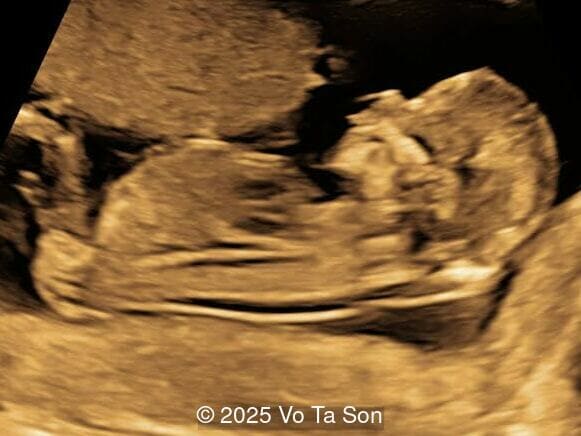

A woman underwent routine prenatal screening at 13 weeks. The non-invasive prenatal test (NIPT) showed low risk for common aneuploidies including trisomy 21, 18, and 13. However, first-trimester anomaly scan revealed multiple fetal anomalies.

We present a case of Triploidy with a 69,XXY chromosomal complement and open spina bifida in the first trimester.

Our imaging revealed the following significant fetal abnormalities:

• Open spina bifida in the sacral region with dry brain sign, crash sign, BS/BSOB >1, and a lesion at the sacral coccygeal spine. The spinal lesion observed in the sacral region is characterized by a posterior vertebral arch defect and a protruding meningeal sac.